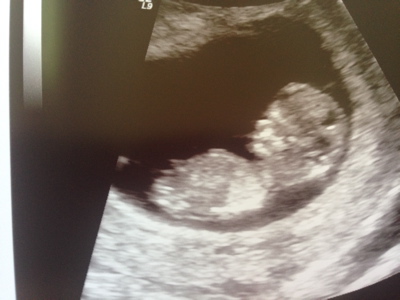

Hello! I'm new to this forum but I'd love to hear what you guess from our 12 week 0 day ultrasound. I really appreciate you taking the time to guess. Skull and Nub guesses would be great! Thanks so much!

Attachment 18913